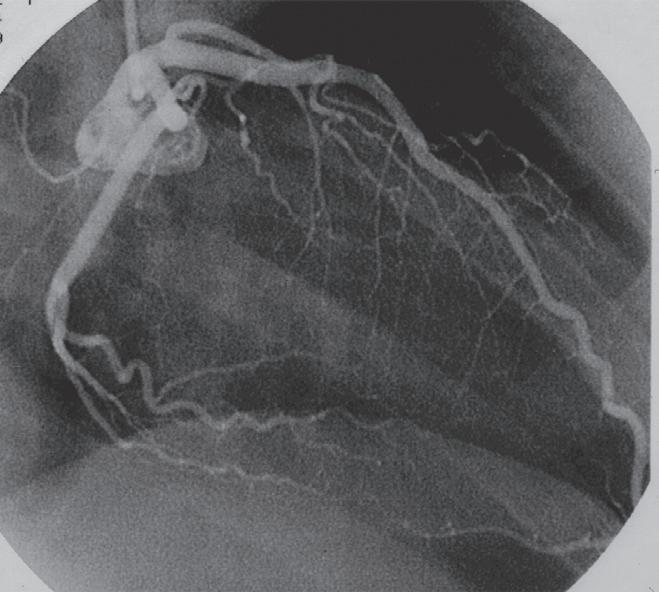

FigurA 3.7 – Angiografia da coronária direita. A e B. Obtida em oblíqua anterior direita (OAD) onde se observa a artéria do nódulo sinusal saindo da porção mais proximal da coronária direita e a artéria do NAV saindo junto à crux cardíaca; C e D . Obtida em OAD caudal onde se observa a artéria do NAV saindo da artéria coronária direita no momento em que dá origem à artéria descendente posterior (crux cardíaca). NS – artéria do nódulo sinusal; NAV – artéria do nódulo auriculoventricular.

NS NAV NS NAV NAV NAV NS NS